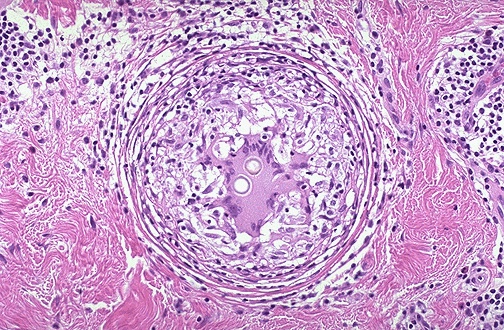

What type of necrosis happening? due to?

Caseous Necrosis, Mycobacteria

Key microscopic features of a granuloma

Pale pink central caseous necrosis, Dark blue lymphocytes, Elongated epithelioid cells, Multnucleated Langhans giant cells.

Cause of granulomatous inflammation

Typical morphology of granuloma

the fungus known as Coccidioides immitis, giant cell in the center, presents

Persistent agents

Rounded and focal nature

Spherules